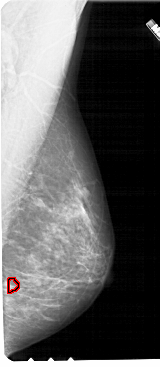

A_1715_1.LEFT_CC

LEFT_CC LINES 4861 PIXELS_PER_LINE 2371 BITS_PER_PIXEL 12 RESOLUTION 43.5 NON_OVERLAY

FILE: A_1715_1.RIGHT_CC.OVERLAY

TOTAL_ABNORMALITIES 1

ABNORMALITY 1

LESION_TYPE MASS SHAPE LOBULATED MARGINS OBSCURED

ASSESSMENT 3

SUBTLETY 3

PATHOLOGY BENIGN

TOTAL_OUTLINES 1

BOUNDARY